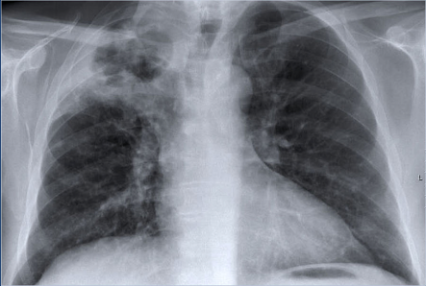

Q

Diagnose?

A

Centralt lokaliseret lungecancer (obs malign tumor i højre hilus)